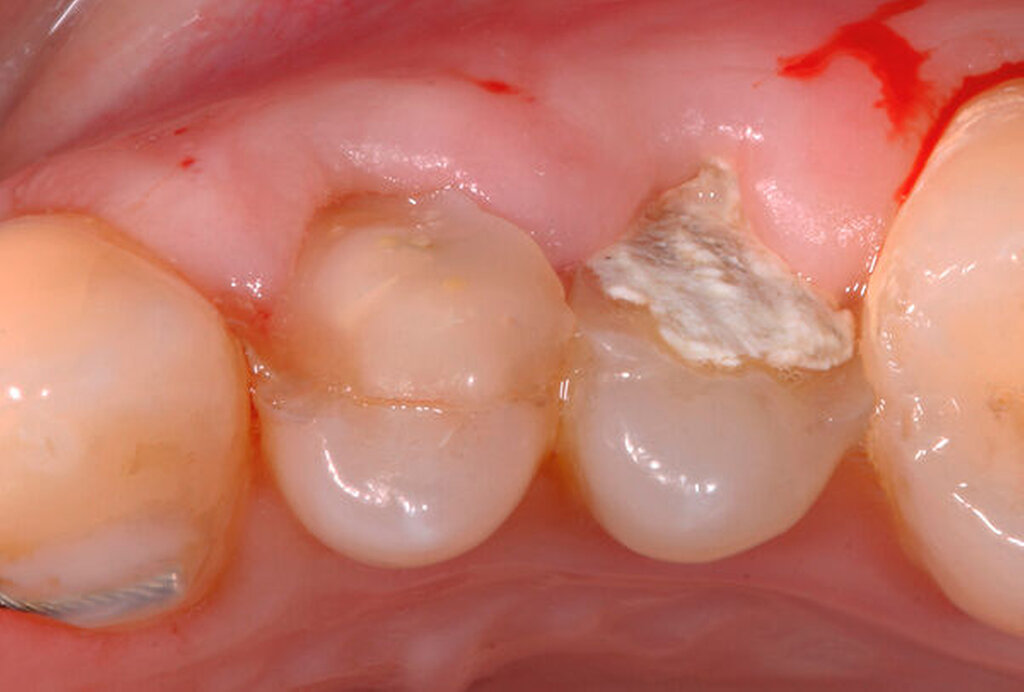

Traumatisierte Zähne mit tiefen, bis zum Alveolarknochen reichenden Defekten gelten als schwer zu restaurieren. In der Traumatologie betrifft dies Kronen-Wurzel-Frakturen oder zervikale Wurzelquerfrakturen. Zähne mit kariesbedingt hohem koronalem Zahnhartsubstanzverlust gehören ebenfalls dazu. Eine sichere Trockenlegung für den präendodontischen Aufbau und eine dichte Kofferdamanwendung sind bei derartig massiv geschädigten Zähnen kaum möglich. Adäquate endodontische Maßnahmen wären somit kaum durchführbar. Zudem gestalten sich sowohl direkte Kompositaufbauten als auch indirekte Versorgungen äußerst schwierig. Wird mit einem krestal gelegenen Restaurationsrand die biologische Breite unterschritten, verursacht dies chronische Entzündungsprozesse. Zudem ist bekannt, dass bei Überkronungen endodontisch behandelter Zähne ein „ferrule-design“ von 2 mm in gesunder Zahnhartsubstanz erzielt werden sollte [Naumann et al., 2018]. Dies sichert eine stabile koronale Restauration und vermeidet maßgeblich den frühzeitigen Retentionsverlust von Zahnersatz. Liegen Defekte vor, die eine Restauration nur unzuverlässig ermöglichen, kann eine Extrusion der Zahnwurzel sinnvoll sein. Hierbei wird der Bereich des tiefsten Zahndefekts durch die Koronalverlagerung möglichst weit iso- oder sogar supragingival positioniert, um somit eine sichere Restaurationsfähigkeit erzielen zu können. Die restaurative Versorgung bei Frontzähnen umfasst abhängig vom Ausmaß der koronalen Destruktion die direkte adhäsive Technik mittels Kompositfüllung oder laborgefertigtem Zahnersatz.

Bei der chirurgischen Extrusion (Synonym: intra-alveoläre Transplantation) wird der betroffene Zahn oder die betroffene Wurzel chirurgisch weiter koronal positioniert, um die Anfertigung einer adäquaten Restauration zu ermöglichen. Ihr biologisches Prinzip ist eingehend beschrieben worden mit guten Erfolgen im Tiermodell [Oikarinen et al., 1996] und in der klinischen Anwendung [Caliskan et al., 1999; Das und Muthu, 1999; Krug et al., 2018]. Die Technik wird bisher kaum in der zahnärztlichen Praxis angewendet, vermutlich aufgrund der begrenzten Vorhersagbarkeit, einen schwer kompromittierten Zahn oder eine Zahnwurzel erhalten zu können, wenn auf konventionelle Art und Weise extrahiert wird. Zum einen besteht das Risiko, durch die Extraktion eine Zahnfraktur zu verursachen, die den Zahnverlust zur Folge hat. Zum anderen führt die Anwendung von Luxatoren, Elevatoren oder Periotomen zu einer Aufdehnung der Alveole sowie zu Schäden am parodontalen Gewebe und gegebenenfalls an der Zahnwurzel selbst. Die Herausforderungen bei einer Zahnmobilisation für eine chirurgische Extrusion bestehen darin, weiteren Schaden an den Strukturen von Zahnhartsubstanz, Knochen und parodontalem Ligament zu vermeiden. Gelingt dies, können deren Hauptrisiken wie Zahnfraktur und progressive Wurzelresorption minimiert werden [Elkhadem et al., 2014].

Zur chirurgischen Extrusion werden meist Extraktionszangen verwendet. Die Zahnwurzel wird dabei idealerweise mit einer diamantierten Zange gefasst und durch Rotation vorsichtig entfernt. Insbesondere bei Zähnen mit runden Wurzeln ist diese Technik auch weitgehend schonend für das parodontale Ligament. Der forcierte Einsatz von Hebeln oder Luxationsbewegungen ist zu vermeiden, da diese zu parodontalen Schäden auf der Wurzeloberfläche führen können und somit die parodontale Heilung nach Replantation gefährden.

Eine weitere Möglichkeit, tief zerstörte Zähne möglichst schonend chirurgisch zu extrudieren, basiert auf axialen Zugsystemen (Abbildungen 2 bis 4). Diese erscheinen vorteilhaft bei sehr schwierigen Fällen, zum Beispiel bei Zähnen mit fehlendem Ansatzpunkt für die Zange sowie bei langen oder sehr ovalen Wurzeln. Axiale Zugsysteme ermöglichen die Übertragung von Zugkräften auf die Zahnwurzel, ohne die Alveole unnötig zu dehnen. Dazu wird eine spezielle Schraube in den Wurzelkanal eingebracht und das Gewinde der Schraube für eine ausreichende Friktion fingerfest eingedreht. An diese Schraube wird ein gerätespezifisches Zugsystem angelegt. Durch rein axial wirkende Zugkräfte werden traumatische Effekte auf Knochen und Wurzeloberfläche während der Zahnmobilisation minimiert. Gegebenenfalls können feine Luxatoren vorsichtig unterstützend eingesetzt werden. Im Tiermodell wurde an extrahierten und wieder replantierten Zähnen mit ovalem Querschnitt gezeigt, dass der Verlust von Zementoblasten auf der Wurzeloberfläche geringer ist, wenn ein axiales Zugsystem anstatt einer Extraktionszange verwendet wird.